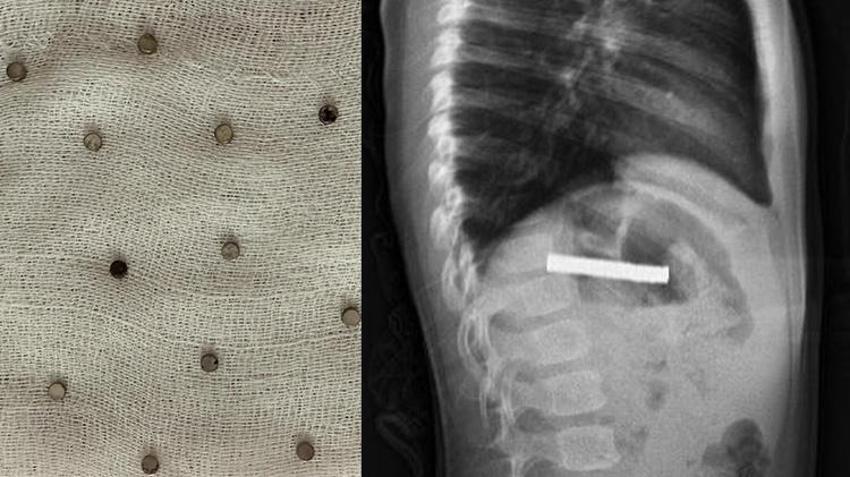

Erzurum'da 3 yaşındaki bir çocuğun yuttuğu 19 mıknatıs, Elazığ’daki Fırat Üniversitesi Hastanesi’nde yapılan başarılı bir operasyonla çıkarıldı.

Yapılan ilk müdahalenin ardından çocuk, ileri tetkik ve tedavisi için Elazığ’daki Fırat Üniversitesi Hastanesi’ne sevk edildi. Fırat Üniversitesi Tıp Fakültesi Çocuk Gastroenteroloji, Hepatoloji ve Beslenme Bilim Dalı Başkanı Prof. Dr. Yaşar Doğan ve ekibi tarafından gerçekleştirilen operasyonla, çocuğun yemek borusuna yapışan 19 mıknatıs endoskopik yöntemle çıkarıldı.

Mıknatısların, mide girişinde ve yemek borusunda zedelenmelere yol açtığı belirtildi. Çocuk tedavisinin ardından taburcu edildi.